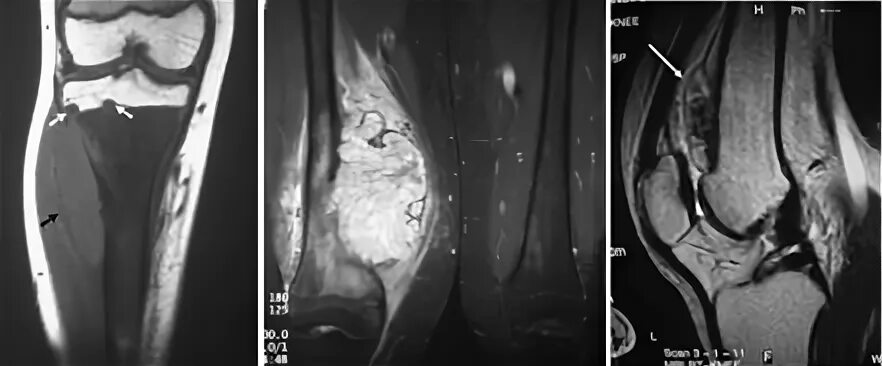

Саркома мрт